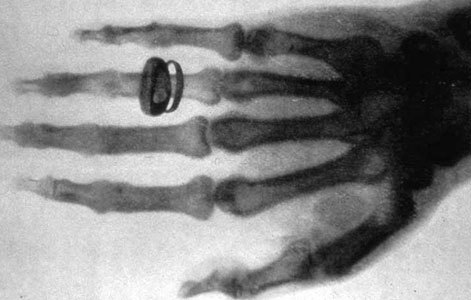

שיטה שימושית מאוד לדימות רקמות קשות. כף ידו של החוקר השווייצרי אלברט פון-קוליקר בצילום שעשה וילהלם רנטגן ב-1896 | מקור: ויקיפדיה, נחלת הכלל